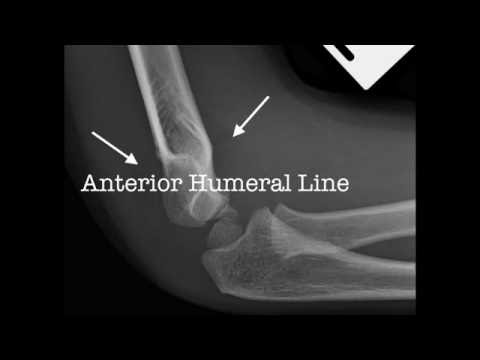

XR | Supracondylar Fractures